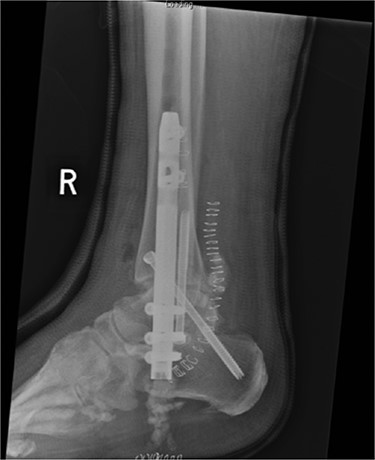

In May 2015, he had a complex midfoot reconstruction, but his foot continued to drift into varus. This was complicated by an infected ulcer on the lateral aspect of midfoot (Fig. 3). Wound infection progressed to osteomyelitis, and in May 2018, he had a hindfoot reconstruction with fusion of tibiotalar and subtalar joints using a Cerament-V-coated hindfoot nail (Figs 4 and 5).

Lateral radiograph of right ankle demonstrating tibiotalocalcaneal fusion using a hindfoot nail and screws.

The nail was inserted under guidance from fluoroscopy. Proximal and distal locking was performed through the standard jigs (Fig. 8).

Clinical photo demonstrating hindfoot nail attached to jig, positioned in hindfoot and the citing of locking screws.